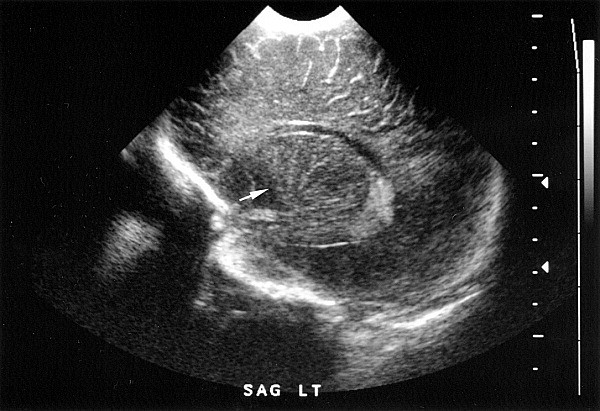

The vasculature supplying the thalamus and basal ganglia is normally indistinct from brain parenchyma on the head ultrasound (HUS) exam of a newborn infant. Recently, however, linear and branching echodensities have been described in the thalami and basal ganglia of a small percentage of infants undergoing HUS examination. This sonographic finding is known as lenticulostriate vasculopathy (LSV, Figure 1). It has been proposed that these bright areas represent a vasculitis of the lenticulostriate branches of the middle cerebral arteries, which occurs in association with a range of perinatal cerebral insults, including infections. LSV has been described with prenatal and postnatal infections,1,2,3,4,5,6 congenital defects,1,2,3,4,6,7,8 infants of diabetic mothers,4,5 and maternal drug exposure3 as well as prematurity.9

Each HUS was reviewed for the presence of LSV by the principal investigator (A. H.). LSV was characterized by the appearance of bright linear echodensities in the area of the lateral striate arteries as seen on sagittal sonographic examination. After a subset of patients with LSV were identified, these infants' HUS were reviewed independently by two other investigators (D. O. and M. M.) for the presence of LSV. LSV was confirmed when all three investigators agreed on its presence on a particular HUS. Each patient with LSV was matched for gender and birth weight (within 10%) with a previously or consecutively admitted premature infant (<35 weeks' gestational age) who had a normal HUS.